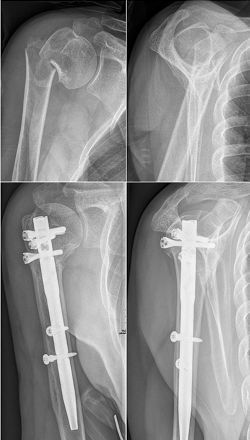

3.钢板螺钉内固定

对于骨质疏松的老年人三部分骨折,选用AO的LCP系统锁定钢板。

6.髓内固定

适应征:The indications for intramedullary locking nail osteosynthesis are three and four-part fractures with metaphyseal comminution or diaphyseal involvement but only minor displacement of the tuberosities. 干骺端粉碎或骨折累及骨干 (结节移位不明显)

髓内固定不足与特点:

-

医源性肩袖损伤(2.6%)

与锁定钢板相比不一定存在优势

对于骨质疏松骨折有较好的生物力学稳定性

总结

切开复位钢板内固定仍是肱骨近端骨折手术治疗的首选

刚柔并济,软硬兼施

要充分了解骨块和对应的肌腱附着

刚性:骨折复位、植骨、内侧支持和钢板坚强固定

柔性:肩袖组织通过缝线技术收拢包裹,减少移位的发生